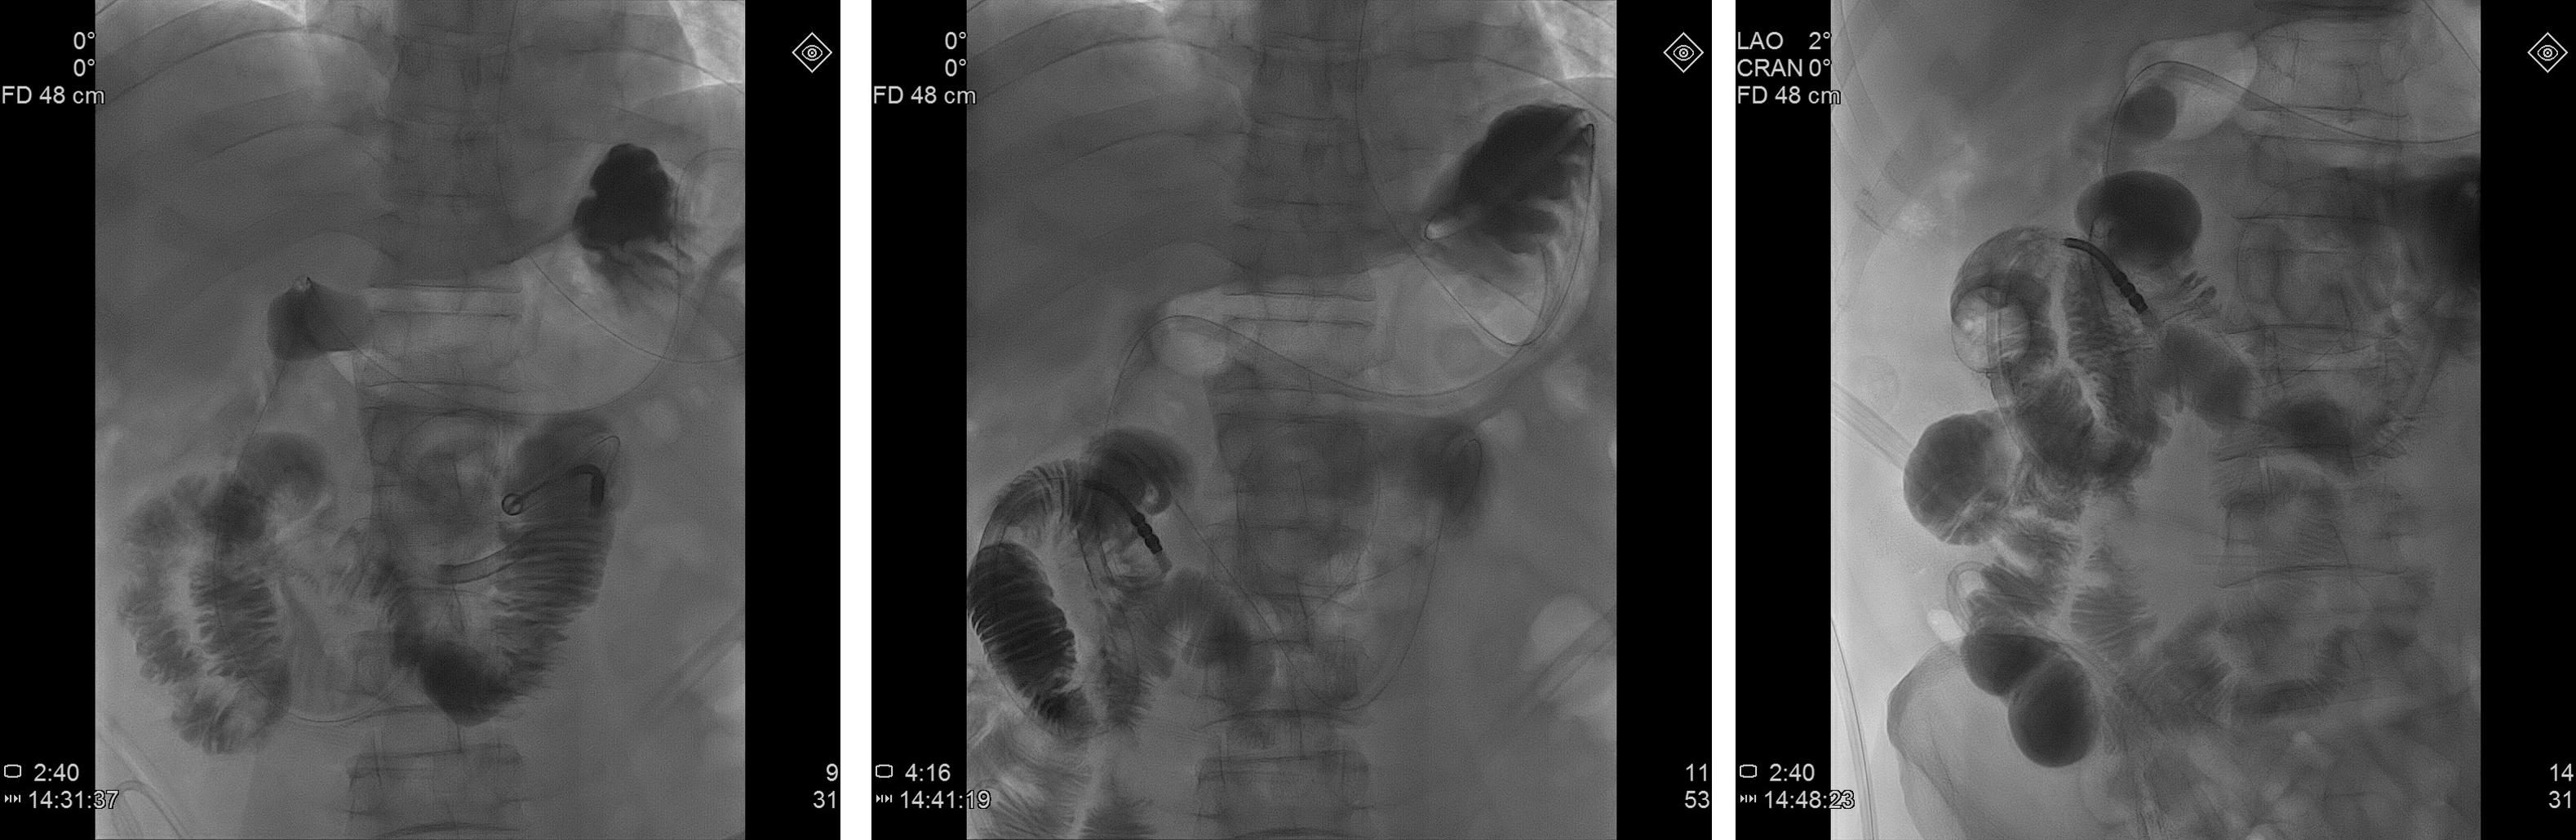

经典病例

中年男性,乙状结肠吻合口瘘术后,腹腔感染,继发粘连性肠梗阻。

立位腹平片

- DSA下行经鼻肠梗阻导管置入,行快速抽吸、减压治疗。